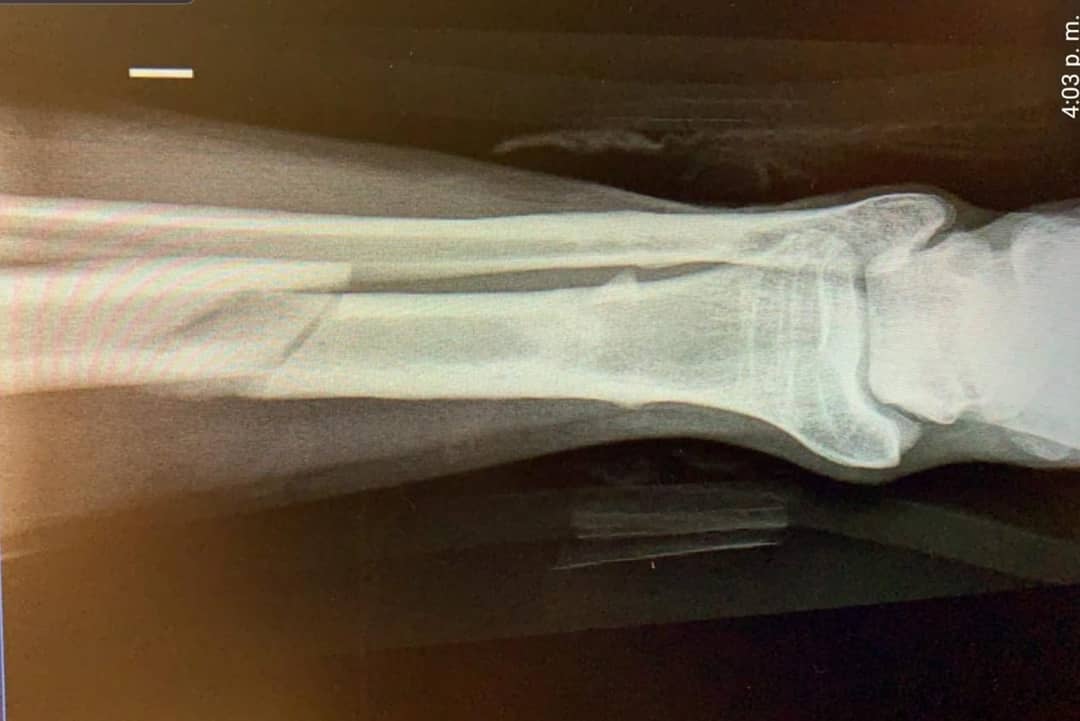

Pero fue este martes cuando Assler volvió a sus redes sociales tras una exitosa operación y entregó detalles de su lesión: fue una fractura de tibia.

El actor compartió fotografías de él en la clínica y también la de una radiografía, en la que se muestra perfectamente la dolorosa lesión.

Matías Assler | Instagram